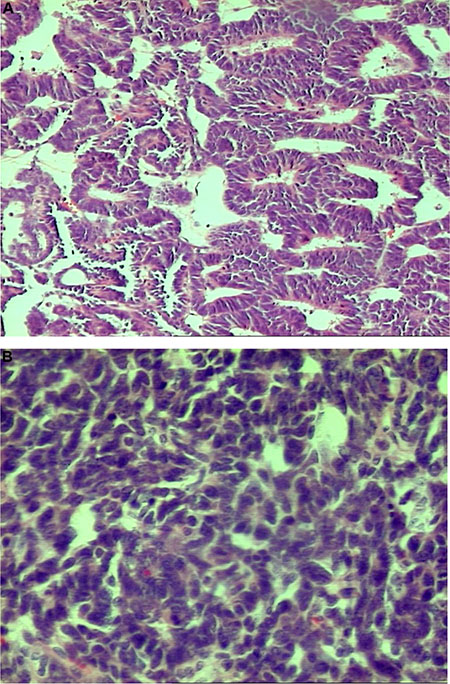

A 1.81% difference was observed in the mean value of delta 15N between a case of Blastemal WT with the features of focal anaplasia (Photo 1) and those without evidence of anaplasia. Similarly, a difference of 3.01% was found for delta 13C between poorly-differentiated epithelial WT and well-differentiated epithelial WT (Photo 2A and 2B). The isotopic studies in the WT group are summarised in Table 2 and Figure 1.

Photo 1: Anaplasia in blastemal type of nephroblastoma – abnormalities of cell nuclei observed in microscopic examination were accompanied by lower values of δ15N and δ13C in comparison with other blastemal WTs (H&E, oryg. magn. 200×).

Photo 2: Nephroblastoma – well-differentiated epithelial type, H&E, oryg. magn. 100× (2A-top) presented higher values of δ15N and δ13C than the poorly-differentiated type, H&E, oryg. magn. 200× (2B-bottom).